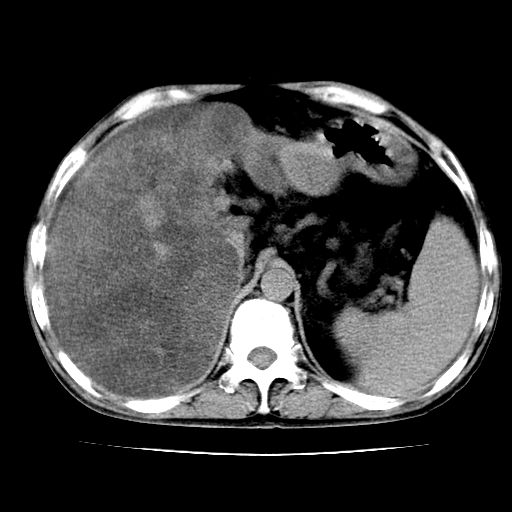

男,55岁,发现“肝硬化”5年,现腰疼、腹胀10余日,巩膜黄染、腹稍胀,肝肋下3指,质硬无压疼,移动性+,血生化:总胆、直胆、间胆均升高。

肝内多发低密度灶(建议增强扫描除外肝癌)

肝硬化,脾大,腹水

脂肪肝

肝占位待排

肝硬化,脂肪肝,腹水,肝癌

腹部病变,ct平扫如同隔靴搔痒,建议增强后上传资料。